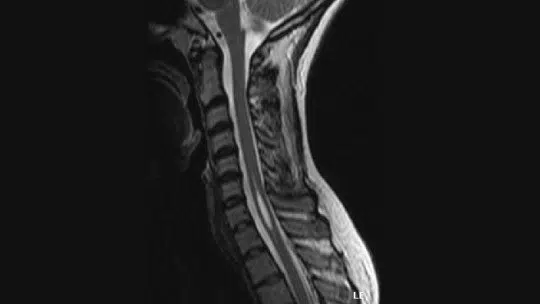

Entenda o que é siringomielia na região cervical da coluna vertebral.

A siringomielia é uma condição médica rara que afeta a região cervical da coluna vertebral. Ela ocorre quando um cisto cheio de líquido se forma dentro da medula espinhal, levando a sintomas como dor, fraqueza e dormência.

As causas da siringomielia podem estar relacionadas a malformações congênitas, lesões na medula espinhal, infecções ou tumores. O diagnóstico geralmente é feito por meio de ressonância magnética e o tratamento pode incluir medicamentos para aliviar a dor, cirurgia para drenar o cisto ou descomprimir a medula espinhal.

Um bom diagnóstico de siringomielia implica que o profissional faça um histórico médico completo e detalhado, acompanhado de um exame físico . Para fazer isso, você pode usar imagens de ressonância magnética da medula espinhal e da medula espinhal, bem como uma varredura usando uma tomografia axial computadorizada que fornece uma imagem detalhada da área afetada.